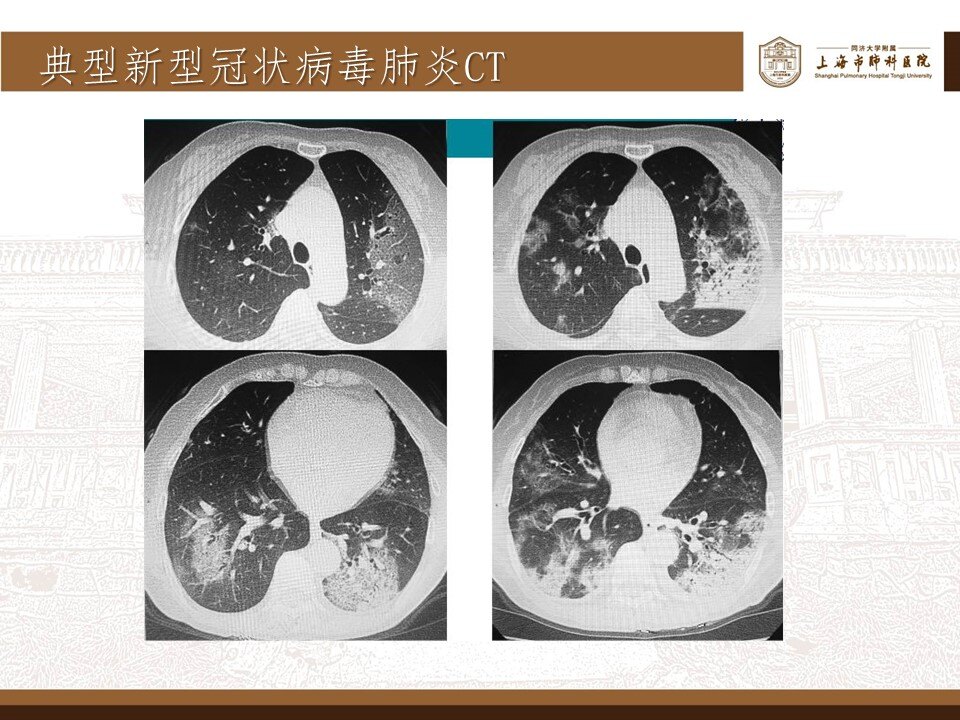

其实,这波omicron感染,确实肺炎比例比想象中要高,但很多都不会是大白肺,多数表现为双肺散发磨玻璃影,当然,也有单独的磨玻璃结节,特别容易表现为混合密度磨玻璃结节。其实很多新发的磨玻璃结节都是新冠肺炎,不用过于紧张,如果感染面积不大,一般临床上,也不需要特异性治疗,休息观察就行了。

可以考虑3个月以后复查一次薄层平扫CT。